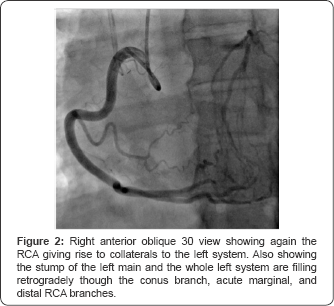

In the ED physical examination revealed blood pressure of 105/54mmHg, heart rate of 90 beats/min, normal heart sounds without any murmur or additional sounds. Lungs were clear to auscultation and there was no peripheral edema. Electrocardiogram revealed sinus tachycardia at ventricular rate 103 beats/min with no ST segment deviations or T-wave inversions. Serial troponins were elevated (highest was 1.13ng/ mL) and chest X-ray was unremarkable. Patient was extubated the following day with return to baseline cognitive function, reported no anginal symptoms prior to cardiac arrest, nor any cardiovascular risk factors. On echocardiogram ejection fraction was estimated at 55-60% without diastolic dysfunction, abnormal wall motion or significant valvular findings. During her hospital stay the patient underwent left heart catheterization through the radial approach. Angiography revealed 100% occlusion of the left main coronary artery at its stump, with collaterals provided by a dominant right coronary artery (Figure 1 & 2).